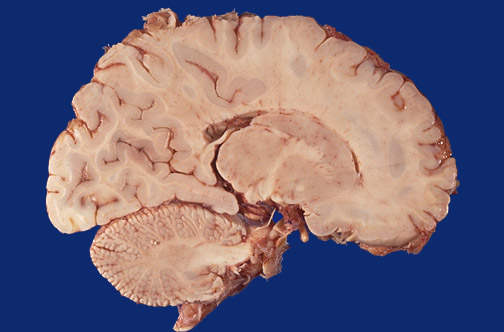

A normal term infant brain is shown in sagittal section near the midline. Identify the following regions in the image above: Caudate - Basal ganglia - Thalamus - Middle cerebellar peduncle - Dentate - Cerebellar hemisphere